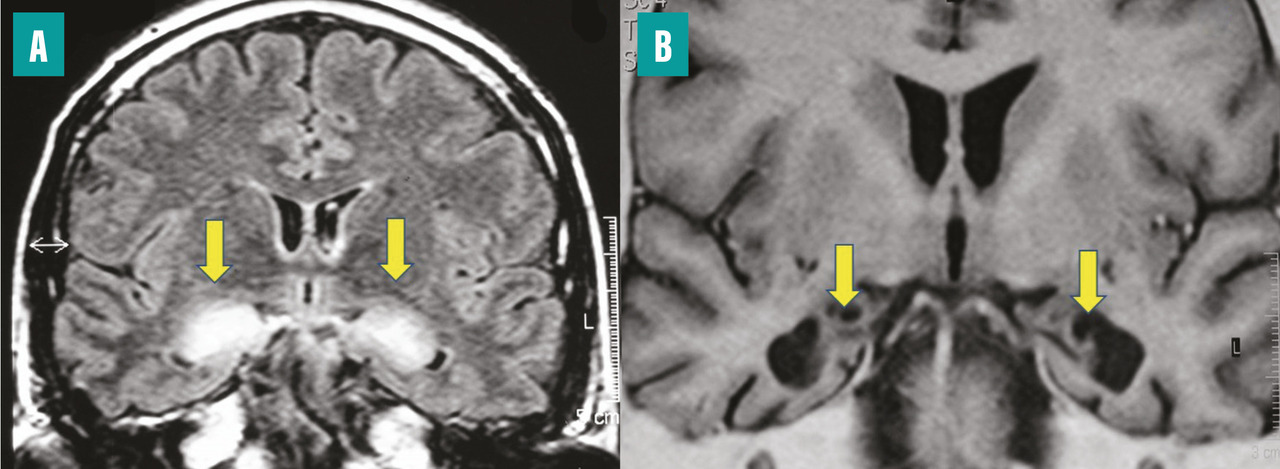

L’extension des DNF dans les hippocampes induit une perte synaptique, puis une mort neuronale, qui finit par engendrer une atrophie hippocampique, visible en imagerie par résonance magnétique (IRM) cérébrale (fig. 1 ). Celle-ci est cependant un signe survenant avec retard par rapport à la clinique. Le défi est de poser un diagnostic de plus en plus précoce de la MA, au stade des prodromes, afin de proposer une prise en charge adaptée.

L’extension des DNF dans les hippocampes induit une perte synaptique, puis une mort neuronale, qui finit par engendrer une atrophie hippocampique, visible en imagerie par résonance magnétique (IRM) cérébrale (